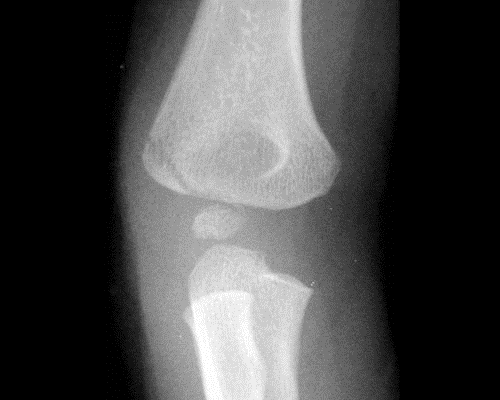

Imaging

• Radiographs

• recommended views

• AP, lateral, and oblique views of elbow

• internal oblique view most accurately shows fracture displacement because fracture is posterolateral

• optional views

• contralateral elbow for comparison when ossification is not yet complete

• routine elbow stress views are not recommended due to pain and lack of useful information

• findings

• fracture fragment most often lies posterolateral which is best seen on internal oblique views

• in displaced fractures, the capitellum is laterally displaced in relation to radial head

• posteriorly based Thurston-Holland fragment on the lateral view